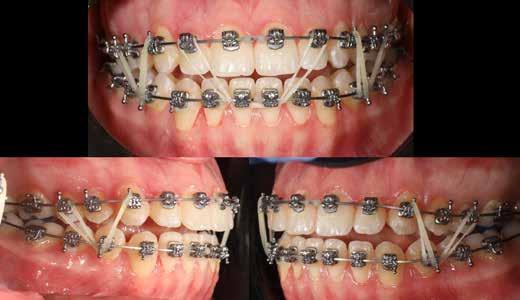

terséges harapásemelés pedig az alsó hatosokra, majd később a felső négyesekre került (8. kép). Az intermaxilláris elasztikus gumihúzás class-2-ess vektorú volt annak érdekében, hogy a disztálharapás korrekciója tökéletes legyen (9. kép). A harapást beállító elasztikus gumihúzásokat – mint minden kezelésnél –, ebben az esetben is folyamatosan, az egész kezelés alatt 24 órában (étkezések kivételével) viselte páciensünk.

A második Pitts-21 fix készülékes fázis ideje 16 hónap volt (10-12. képek)